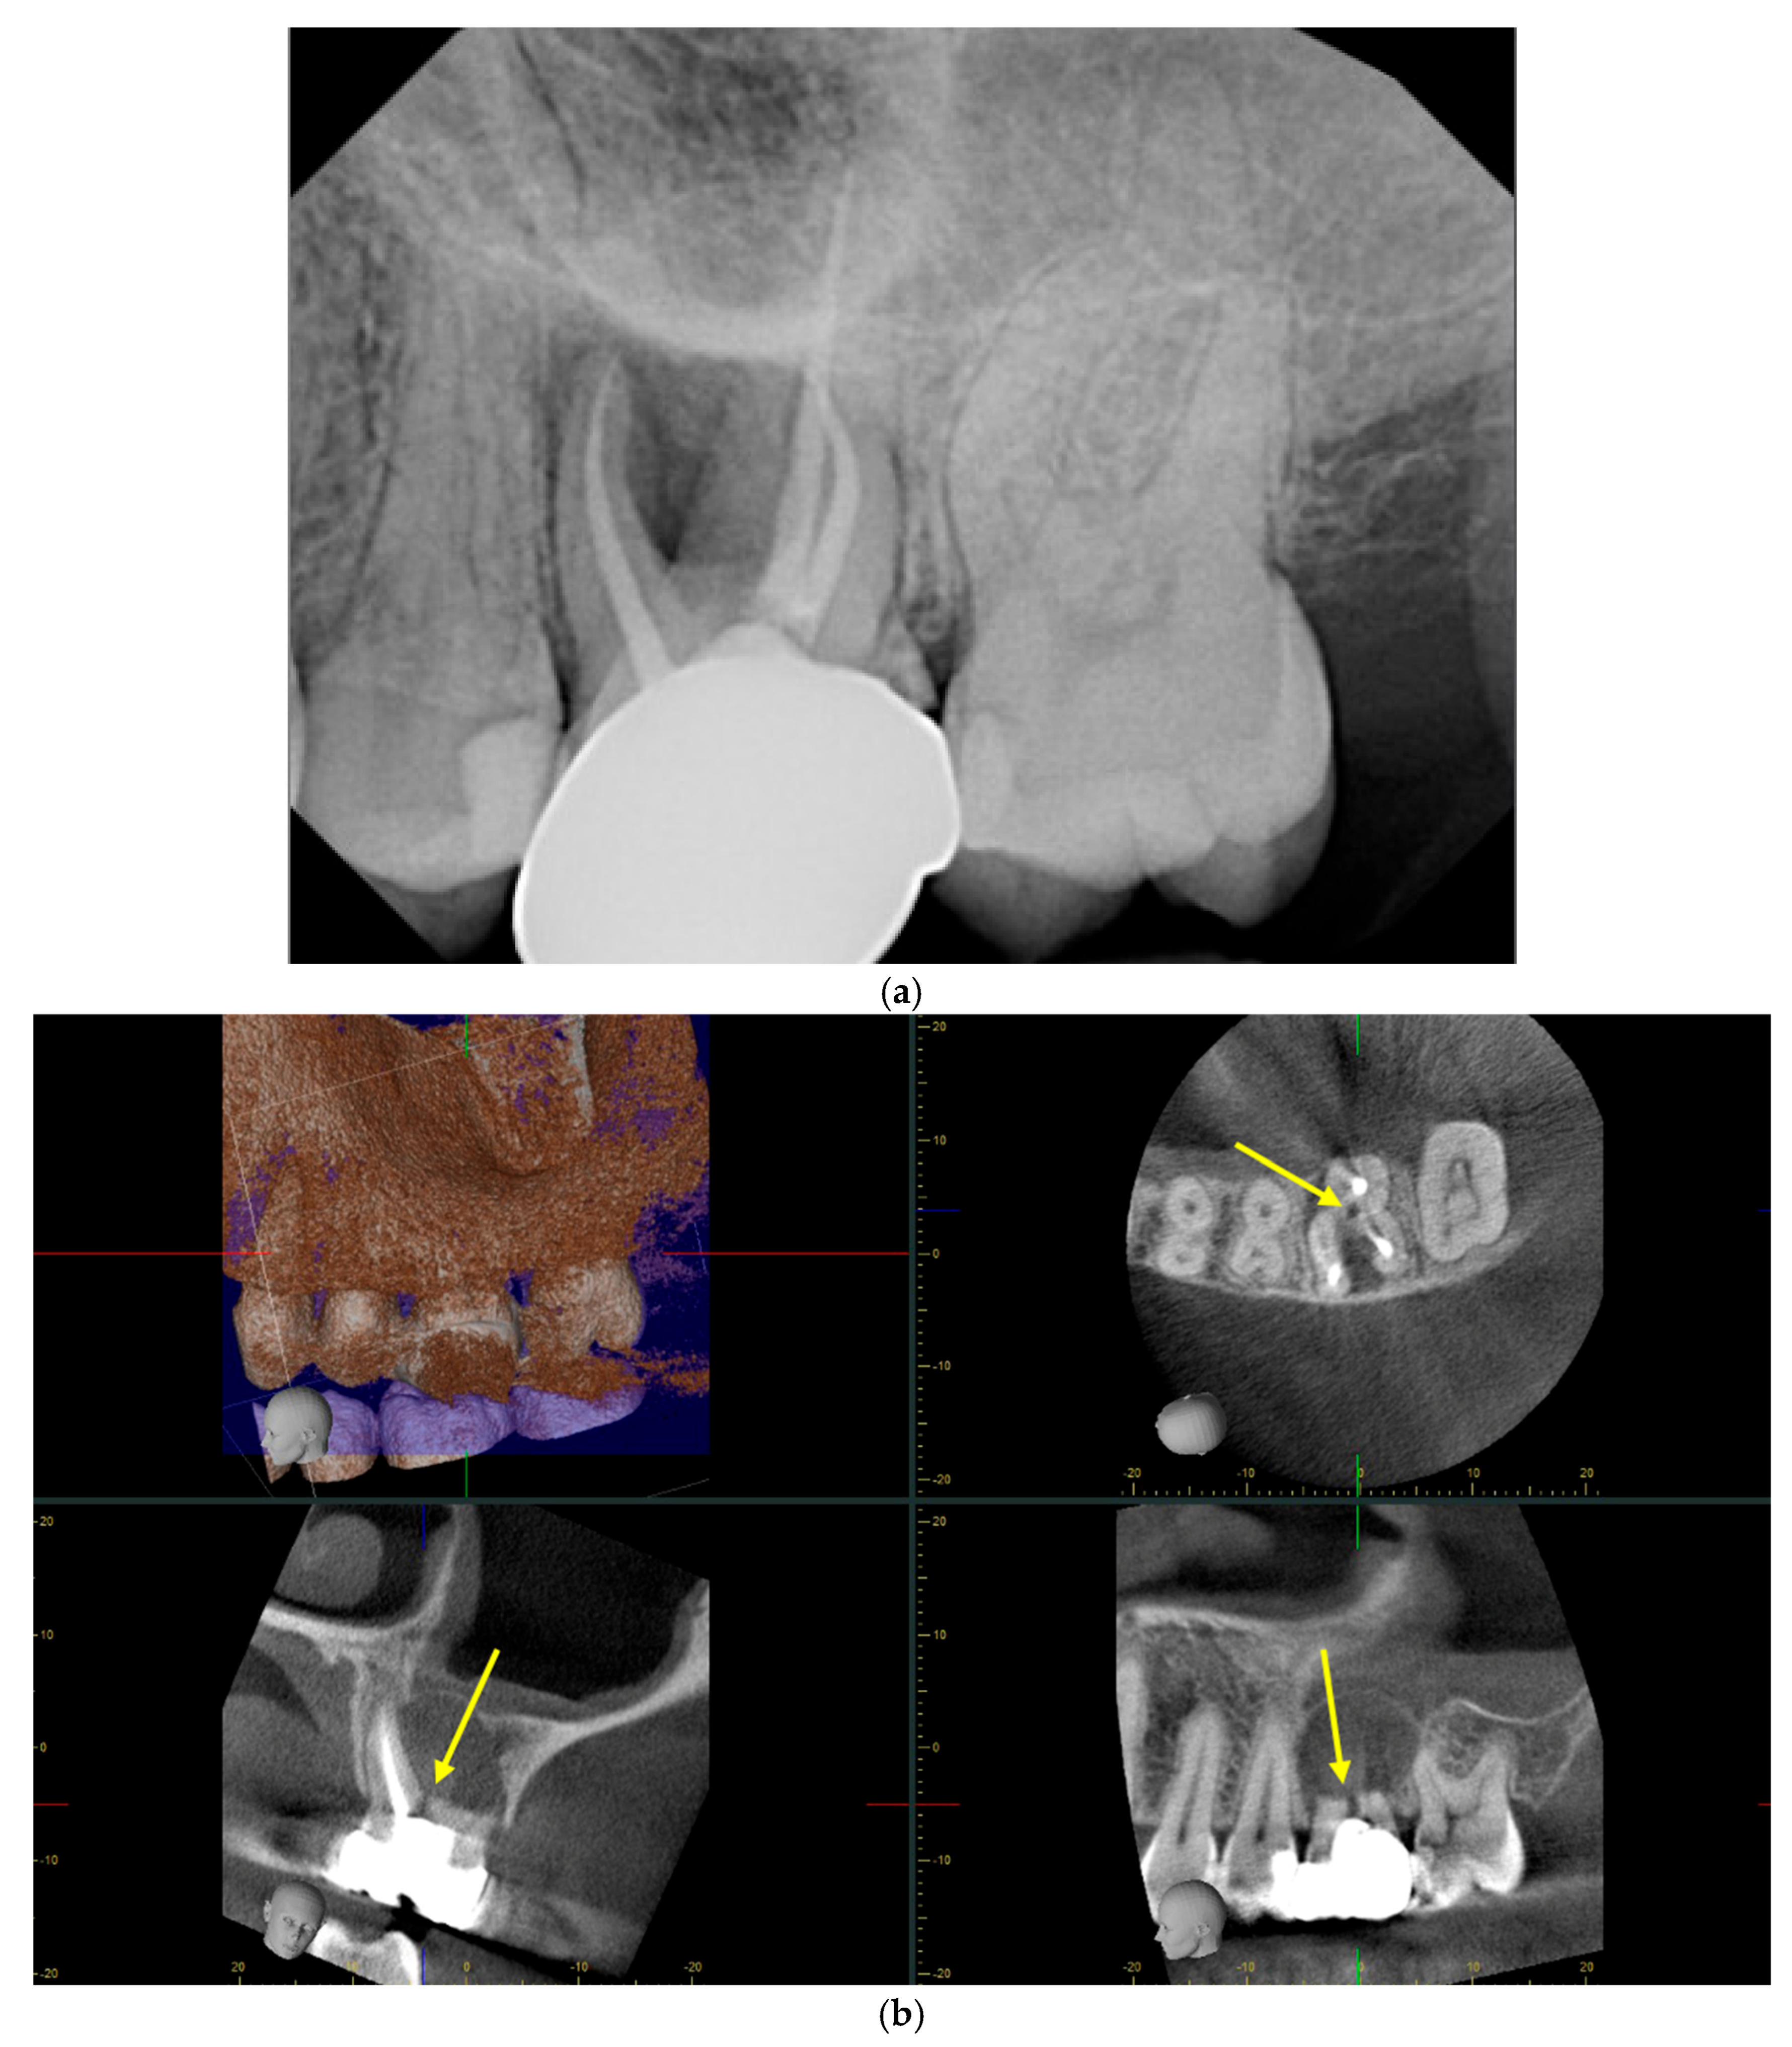

4.6. Radiographical Diagnosis

4.7. CBCT versus Periapical Radiographs